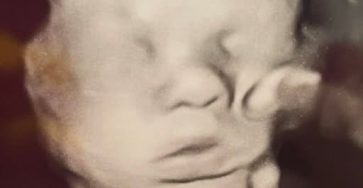

Modelos 3D para Cirugías Fetales: Una Revolución Médica que Comienza Antes del Nacimiento

El avance de la tecnología médica ha permitido logros que, hace solo unas décadas, eran impensables. Uno de los más…